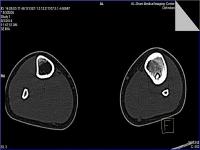

(#0104) CT Osteoid Osteoma